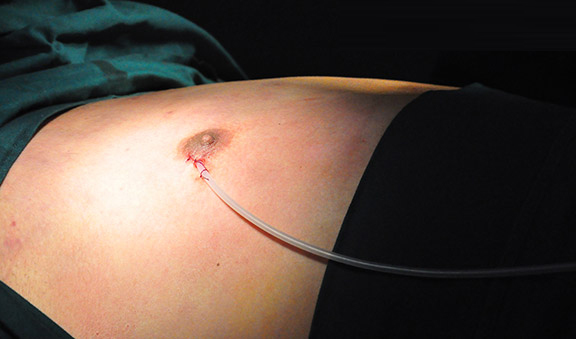

案例三

患 者:小刘(化名) 15岁(男)

主 诉:三年前发觉自己的胸部开始微微隆起,以

为发胖所致,从小馒头变至充气的皮球一样大

诊 断:男性乳房发育症

治疗方案:针孔清除术

治疗状况:术后恢复正常,无反复

案例四

患 者:小吴(化名) 19岁(男)

主 诉:胸部长了一对令女人羡慕的大乳房,2年

前进行过胸部手术,又复发

诊 断:男性乳房发育症

治疗方案:针孔清除术

治疗状况:手术成功,恢复正常生活